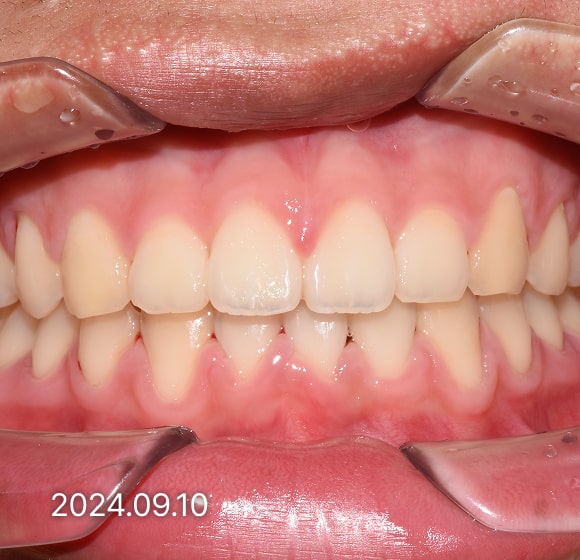

BEFORE / AFTER

전후 변화로 보는 치료사례

본 사진은 진심을담은치과교정과 치과의원에서

치료한 환자의 동일 인물 전·후 사진입니다.

개인의 구강 상태 및 관리 방법에 따라 통증 및 잇몸 염증,

턱관절 불편감 등의 부작용이 발생할 수 있습니다.

치료 전 치료 후

덧니, 삐뚤한 치열

돌출입

반대교합(비수술)

성장기 교정

과개교합

개방교합

치열공간, 벌어진 앞니

매복치아

악교정 수술 교정

결손치

부분교정

인비절라인